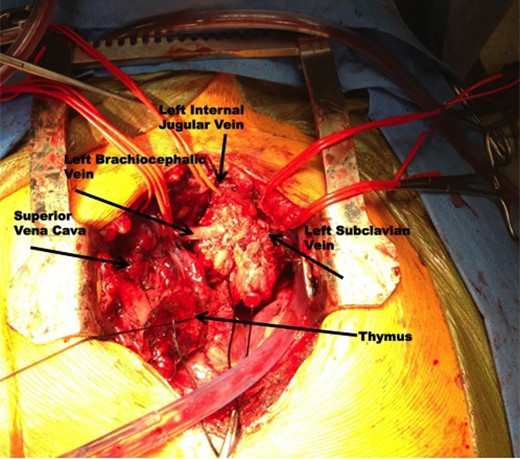

A 17-year-old male presented with complaints of left-arm swelling and occasional pain. Imaging obtained of the chest and neck revealed a large anterior mediastinal mass involving the major venous structures of the left chest (Fig. 1). Computed tomography (CT)-guided needle biopsy was performed, with inconclusive results, and this was followed by a left video-assisted thoracoscopic surgery (VATS) procedure yielding enough tissue for formal diagnosis of an epithelioid hemangioendothelioma. After extensive multidisciplinary consultation and preoperative planning, the patient was taken to the operating room for a median sternotomy, thymectomy and en-bloc excision of the tumor and vessels (Fig. 2). Vascular reconstruction of the left brachiocephalic and left subclavian vein was performed with an 8 mm ringed polytetrafluoroethylene graft, with an additional end-to-side anastomosis of the left internal jugular vein to the graft. The patient tolerated the initial procedure well, was extubated on postoperative Day 1 and advanced to an oral diet. After several days, large-volume milky drainage from the chest tube was evaluated and presence of a chyle leak confirmed. The patient returned to the operating room on postoperative Day 6 for a right VATS with ligation of the thoracic duct. Final tumor measurements were 7.5 × 5.5 × 3.5 cm, and final pathology confirmed an epithelioid hemangioendothelioma with no mitoses, <5% necrosis and a final pathologic staging of pT2b. The patient has since recovered uneventfully and was discharged home in stable condition.

Intraoperative photography demonstrating the epithelioid hemangioendothelioma encasing the left brachiocephalic vein, left internal jugular vein, and left subclavian vein.